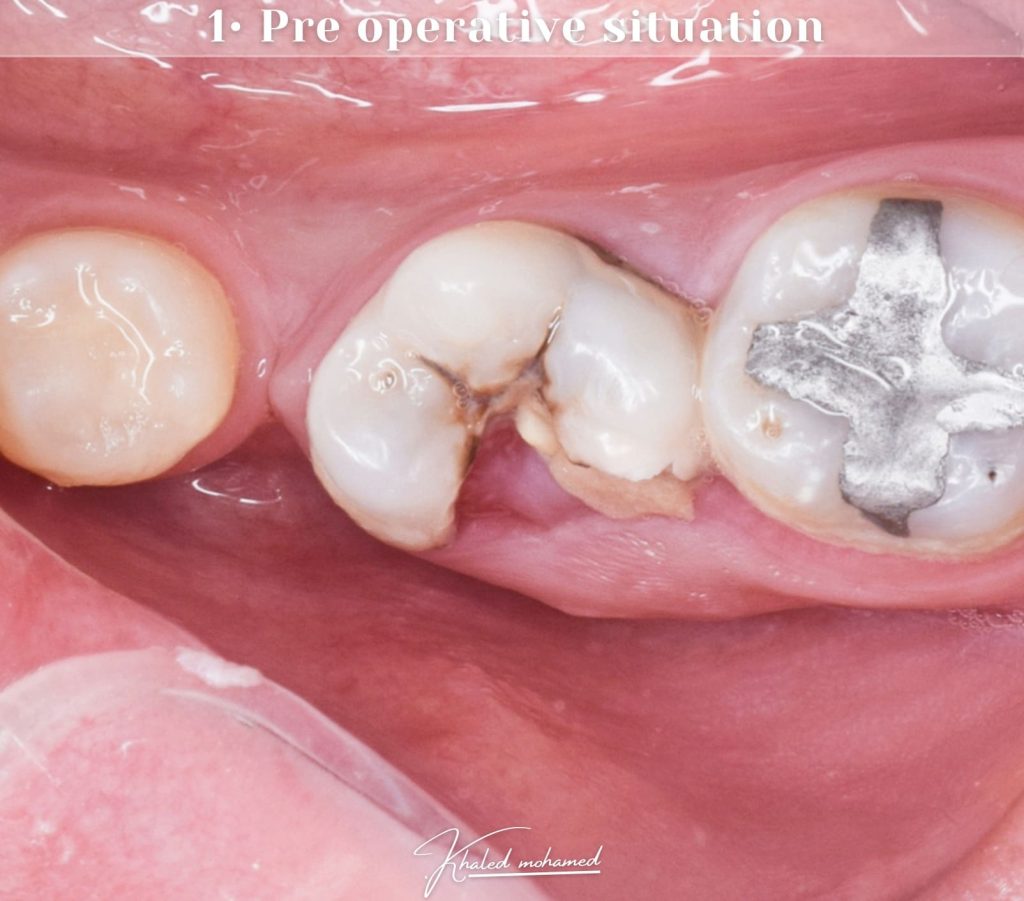

Pre operative situation

A 16 years old male patient visit our clinic complain from sever pain and food impaction. After diagnosis i confirmed that his tooth need RCT